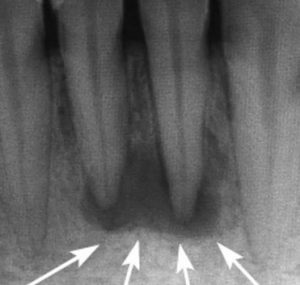

Первым делом врачу нужно поставить точный диагноз и удостовериться, что образование действительно является гранулемой. Для этого ему необходимы рентгеновский снимок и результат гистологического исследования. Как только диагноз будет установлен, доктор выберет тактику лечения.

Раньше считалось, что кисту от гранулемы можно отличить по размерам (киста крупнее, чем гранулема). Однако такое мнение ошибочно. Гранулема вполне может вырасти до размеров кисты. Для постановки правильного диагноза одного рентгеновского обследования мало. Необходим анализ на гистологию.